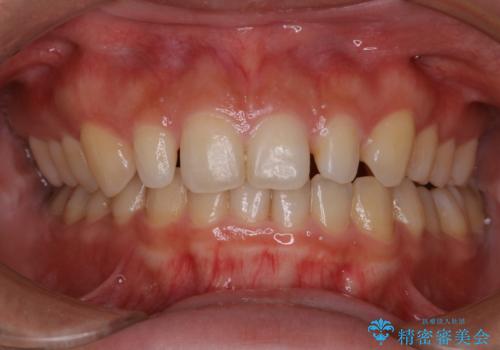

前歯のセラミック製作前にPMTC

- 前歯のすき間をセラミックで治療するため、処置前にクリーニングを希望されました。PMTC30分コースを行いました。

PMTCは、国家資格取得者の歯科衛生士により、専門的な機械や材料を使用してのクリーニングです。一人一人の患者様のお口の状態に合わせたクリーニングを行います。

セラミック治療などの際に歯肉が腫れていたり、治療中に出血したりすると

、精密に型取りができなかったりすることがあります。

PMTCを行うことで、歯肉の引き締まりも期待できます。治療前にもPMTCを行うことはおすすめです。